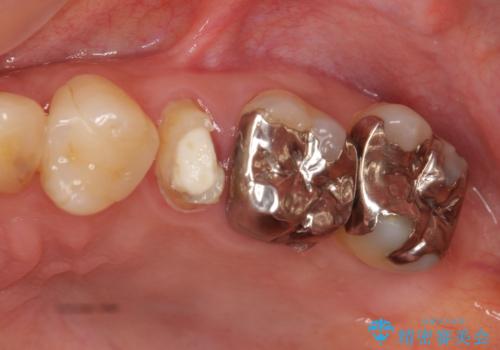

- 左上5番の根の治療途中で転院希望で来院。

割れているために抜かないといけないと説明されたとのことでした。

特に割れている所見はなかったため、根の治療から被せ物まで治療を行いました。

奥の銀歯のやりかえも希望されたため、セラミッククラウン、インレーにする治療をしています。